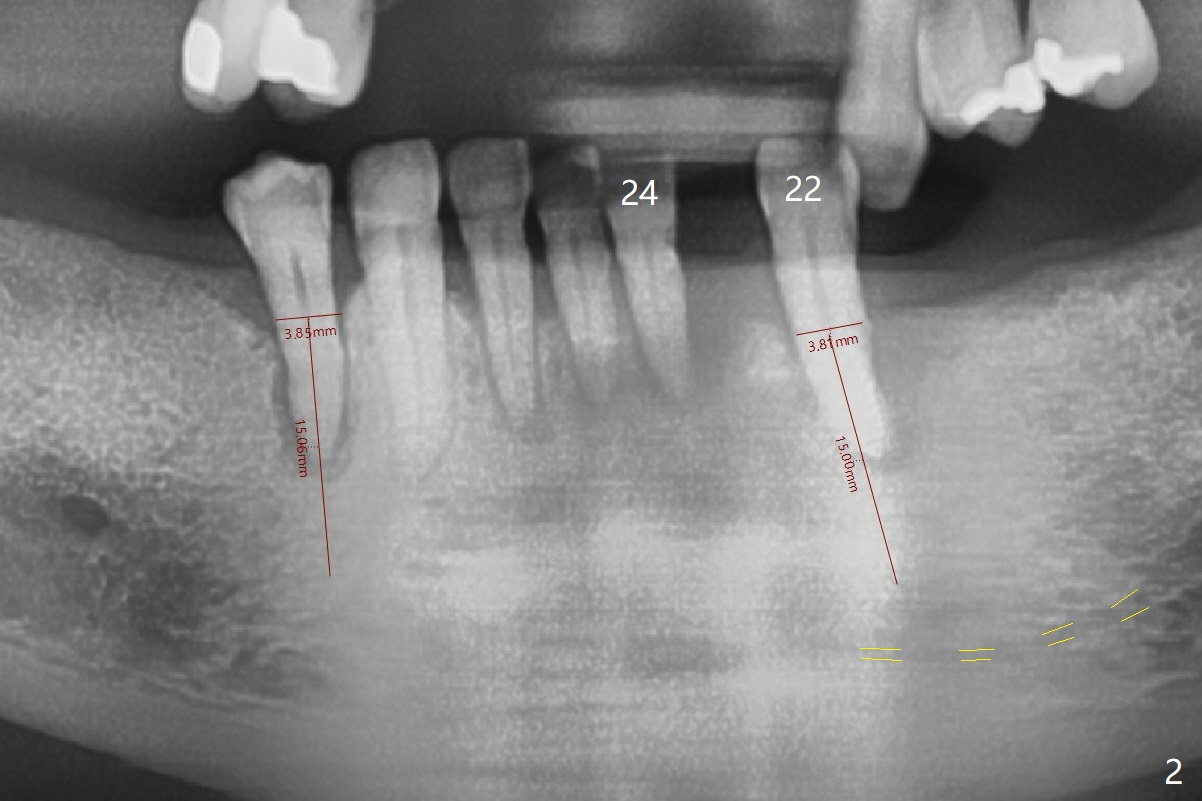

A 50-year-old woman (dentophobic, smoker, 1/3 pack per day) has chronic periodontitis with terminal dentition (Fig.1). Provisional RPDs are 5 years old. Before fabricating permanent RPDs, nonsalvageable teeth, for example #22, should be extracted and replaced with an implant with ball abutment (Fig.2). Because of fear and finance, one implant will be placed each time.